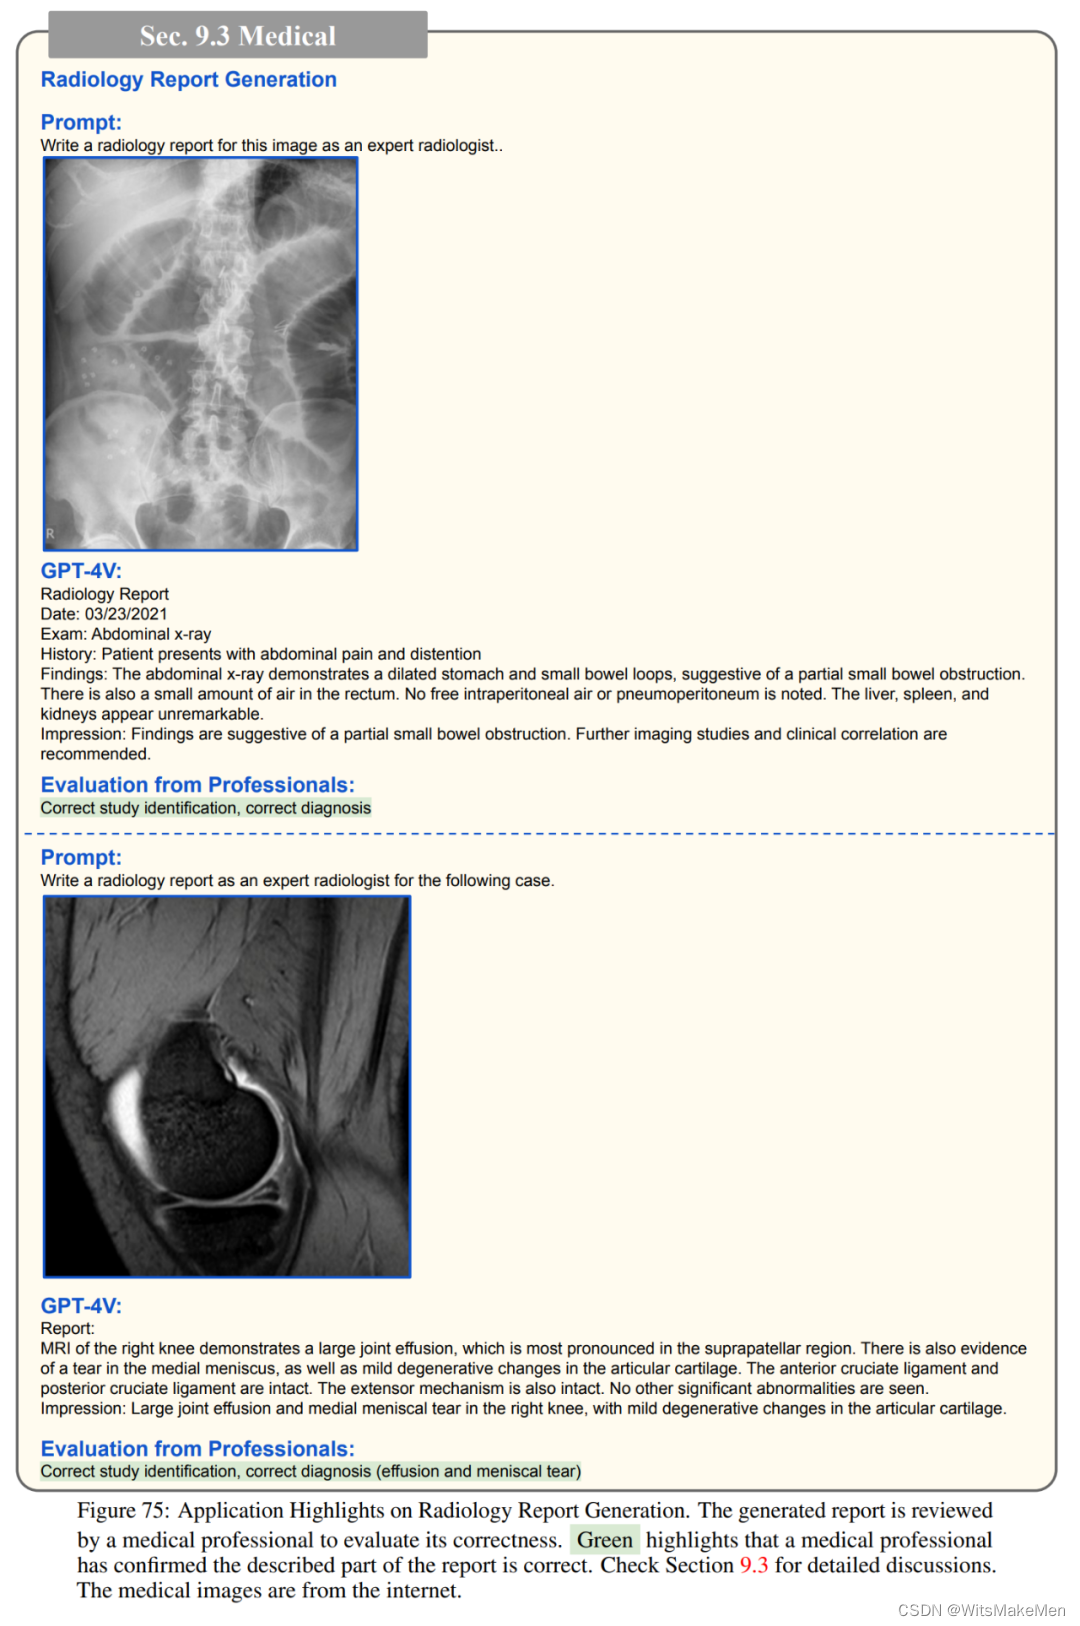

医药